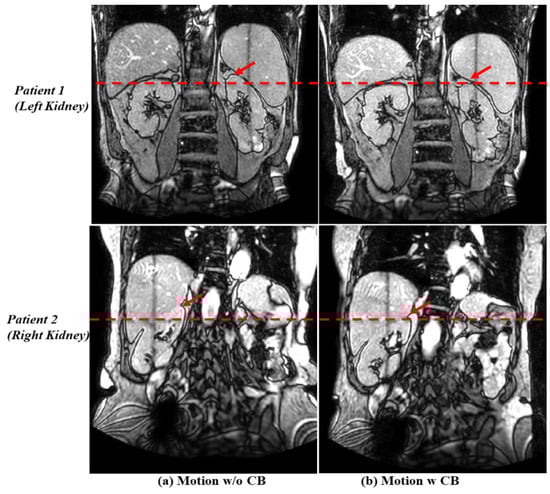

3.2. Motion Management with the Compression Belt